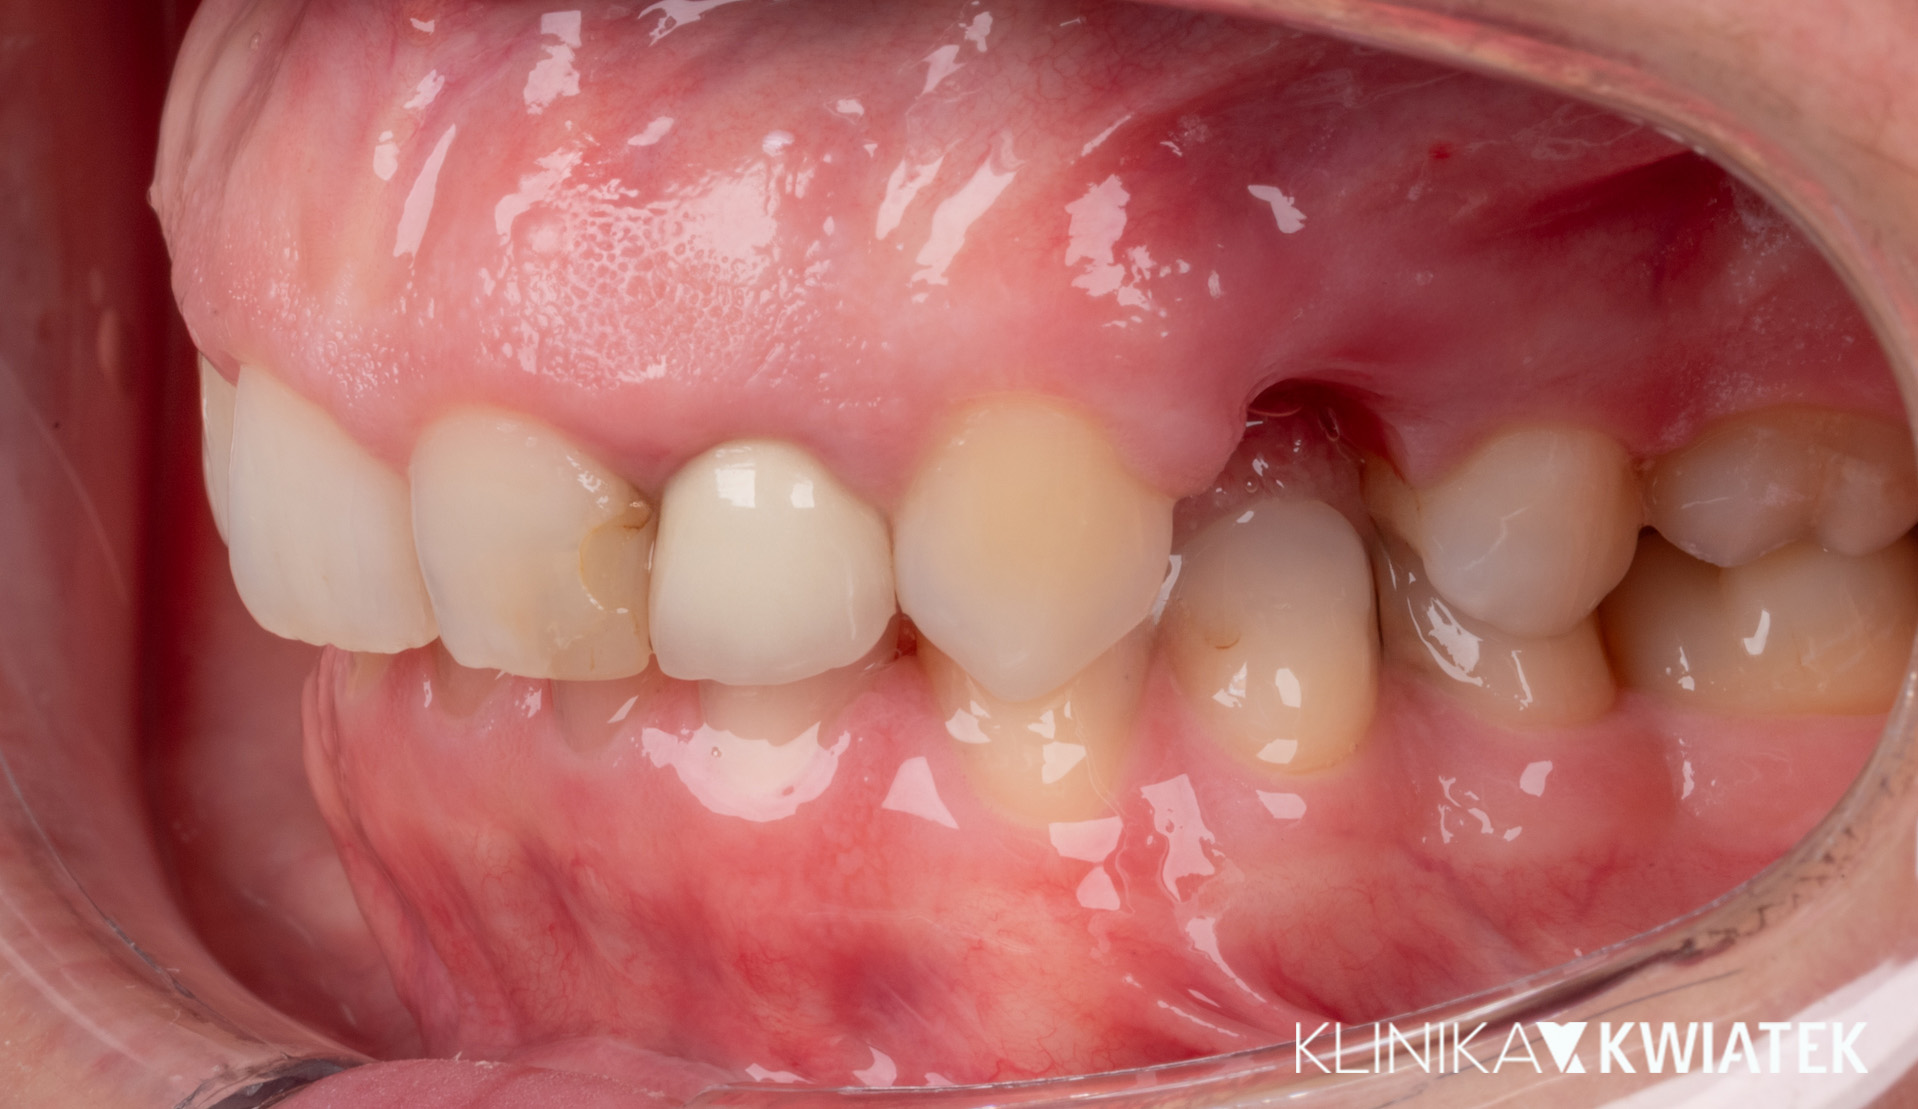

Jak uśmiech pokonał strach – metamorfoza pełna zaufania

Pacjent przez wiele lat unikał wizyt u dentysty z powodu silnego lęku. Strach przed leczeniem sprawił, że w jamie ustnej pojawiły się rozległe zmiany próchnicowe i liczne zęby wymagały ekstrakcji.

Po dokładnej diagnostyce i rozmowie, wiedząc, że Pacjent wyklucza leczenie ortodontyczne, krok po kroku wdrożono kompleksowy plan leczenia – od higienizacji i leczenia zachowawczego, przez zabiegi chirurgiczne i endodontyczne, aż po odbudowę braków zębowych na implantach.

Dziś Pacjent z dumą i spokojem uśmiecha się bez lęku – cieszy się zdrowym, estetycznym uśmiechem, stabilnym zgryzem i doskonałą higieną jamy ustnej.